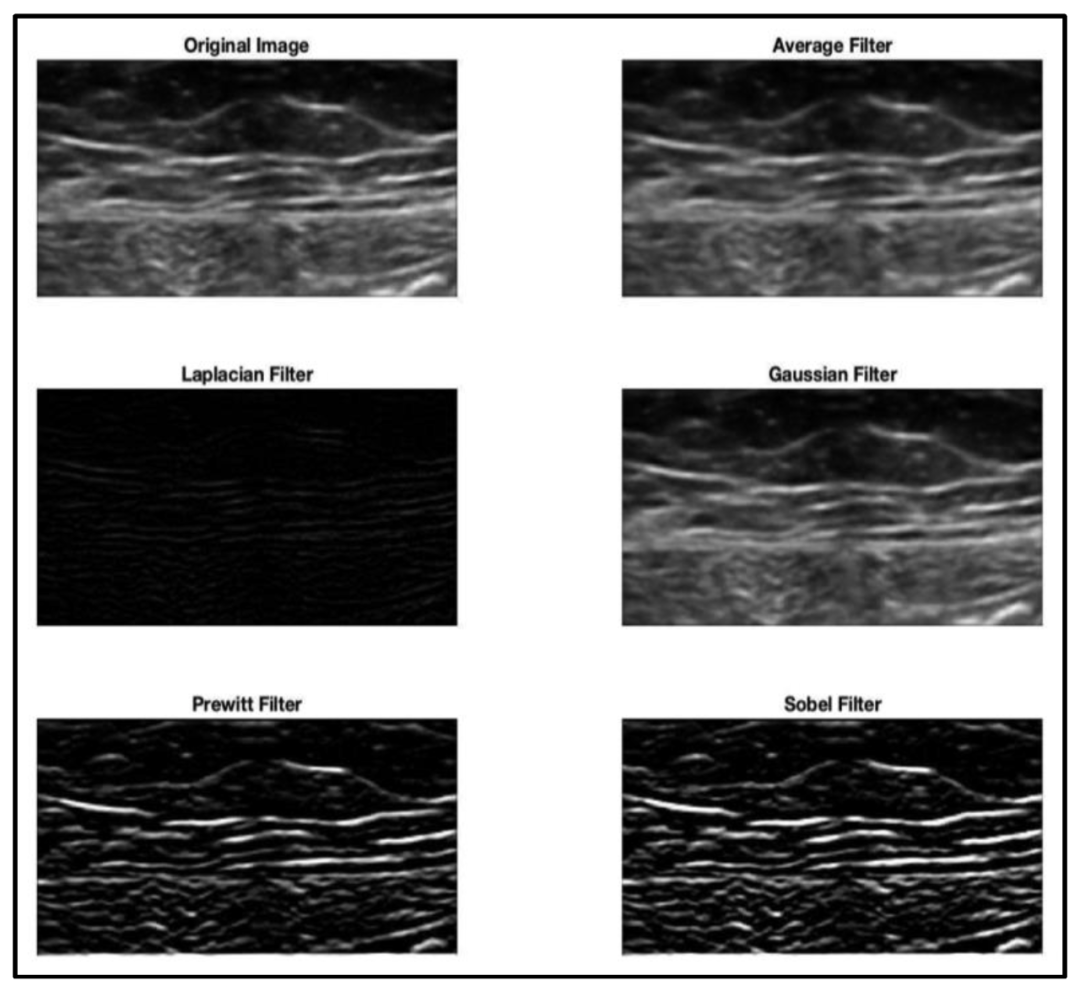

過半的研究者在深度學(xué)習(xí)訓(xùn)練之前,實施了預(yù)處理。最常見的比如歸一化;直方圖均衡化,用于通過擴展圖像的強度值來增加圖像的對比度;以及基于強度/尺度的濾波(見圖2)。

圖2 :圖像預(yù)處理:應(yīng)用于原始圖像的濾波技術(shù)